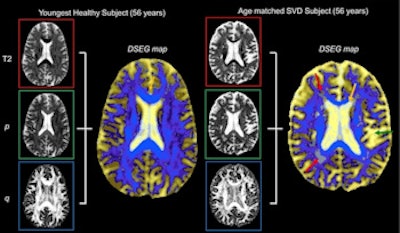

Diffusion tensor image segmentation color maps of the brain from healthy subject and age-matched SVD subject. By overlaying T2, p and q images, brain sensitive alterations in brain microstructure are visible. Red arrows indicate white matter hypersensitivities; orange arrow shows corpus callosum; green arrow shows the greater volume of cerebrospinal fluid space. © 2017 The Authors (CC BY-NC-ND 4.0).

The DSEG technique enables imaging of gray matter, white matter, cerebrospinal fluid, and white matter hypersensitivities, which when combined to create a DSEG Θ angular score can quantify brain damage effectively. The authors note a limitation of this study is the lack of consideration for the spatial location of SVD-related pathology.